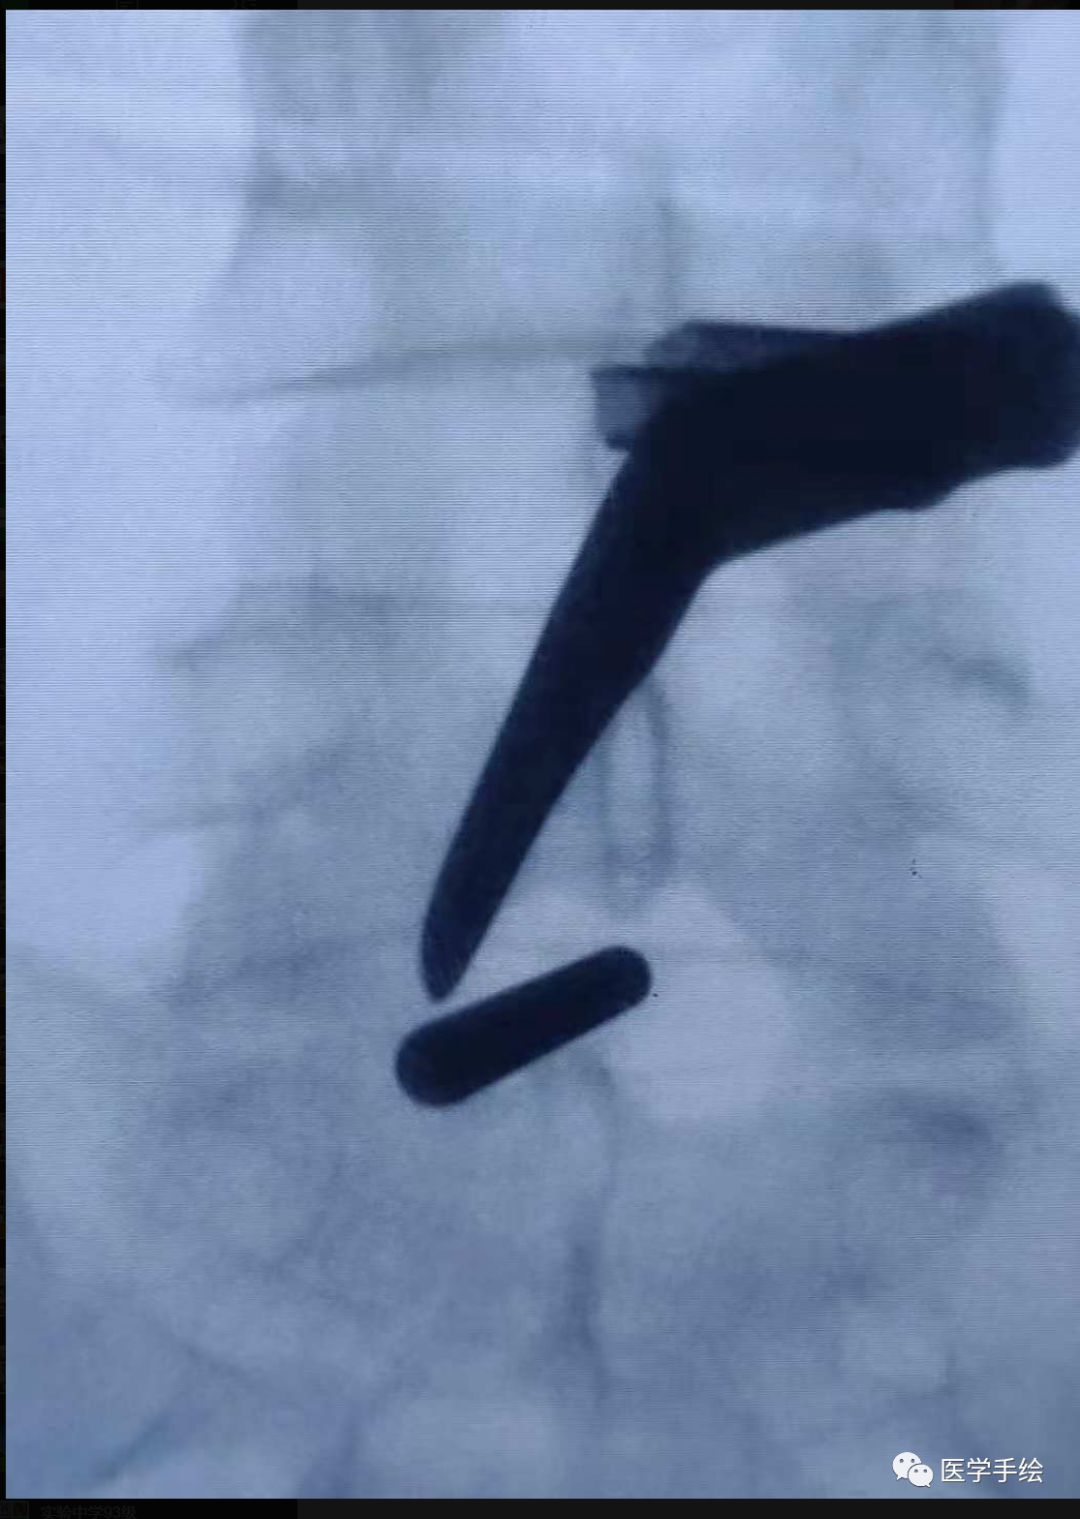

2、专门器械包内包含扩张导管及特制的剥离器,本病例的剥离器为模仿自制器械。扩张导管及剥离器的作用是通过扩张及骨面的剥离来创造一个工作空间。这一步骤非常重要,做好了事半功倍。